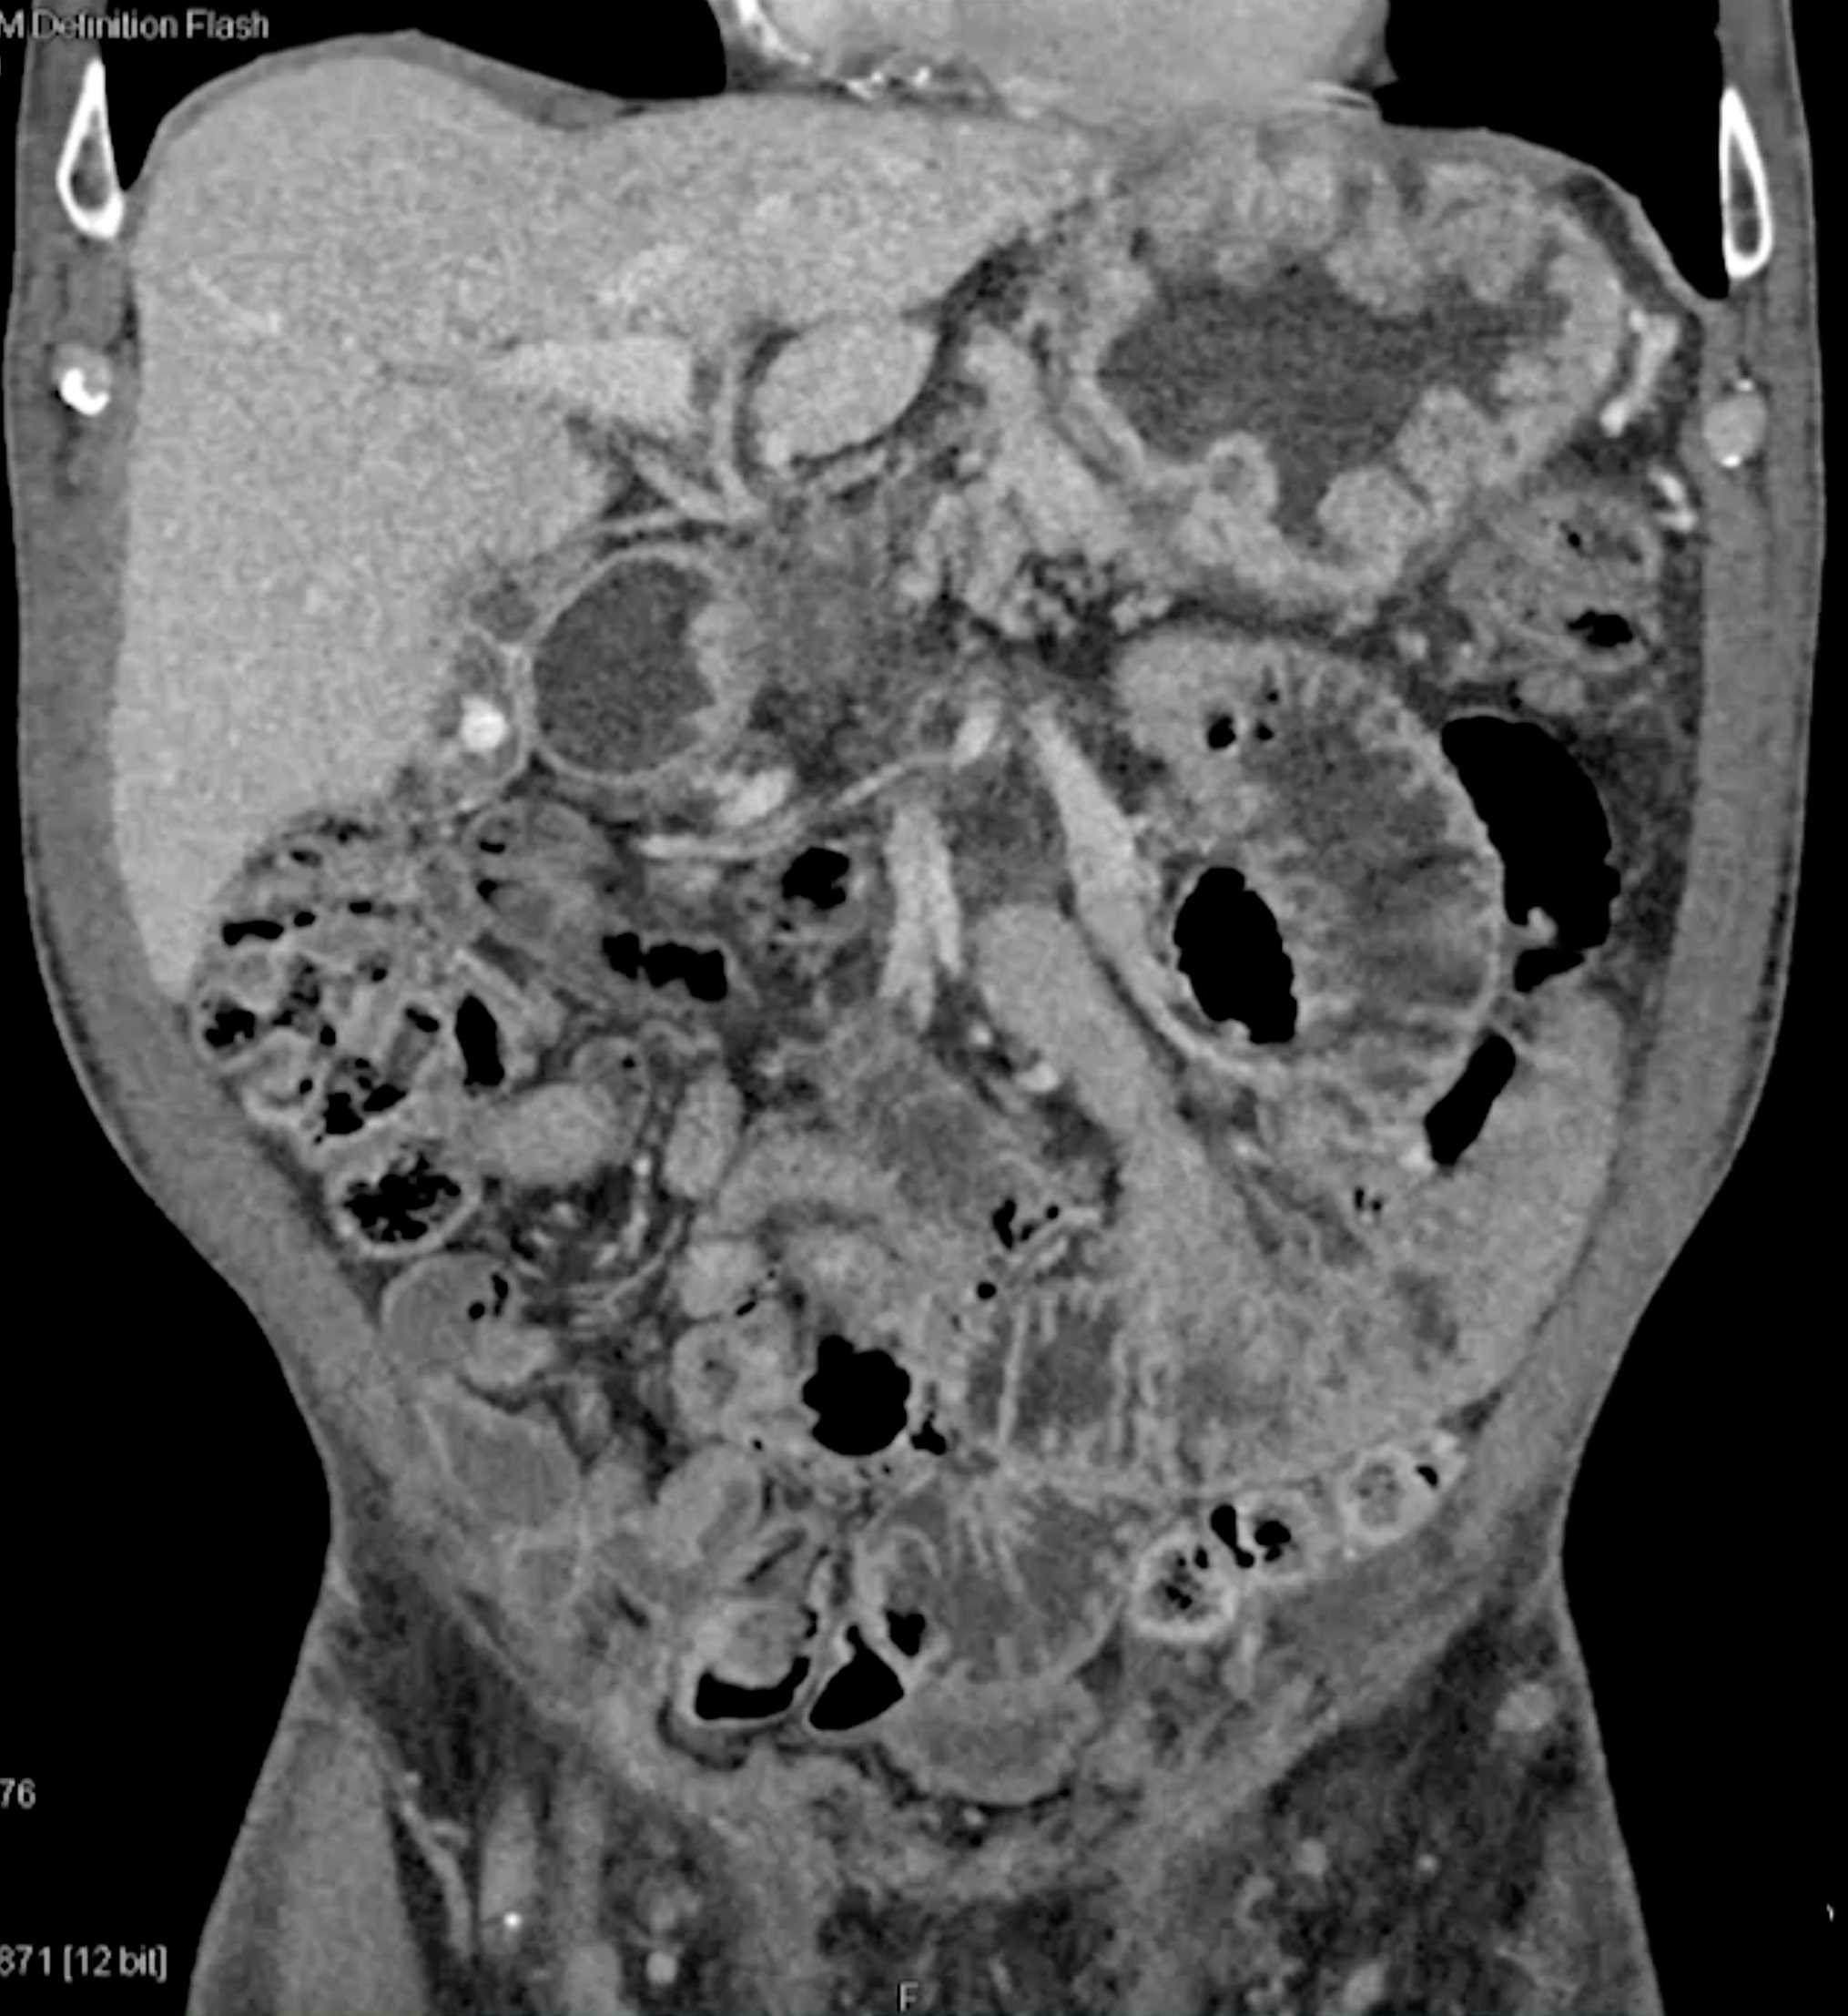

Chemical Gastritis due to NSAIDs